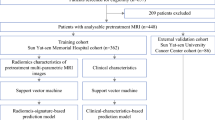

This monocentric retrospective study included 75 TN female patients with MRI (T1-weighted, T2-weighted, diffusion-weighted and dynamic contrast enhancement images) performed before NAC. For each patient, the tumor(s) and the parenchyma were independently segmented and analyzed with radiomic analysis to extract shape, size, and texture features. Several sets of features were realized based on the 4 different sequence images. Performances of 4 classifiers (random forest, multilayer perceptron, support vector machine (SVM) with linear or quadratic kernel) were compared based on pathological complete response (defined on the excised tissues), on 100 draws with 75% as training set and 25% as test.

Liu Z, Li Z, Qu J, Zhang R, Zhou X, Li L, Sun K, Tang Z, Jiang H, Li H, Xiong Q, Ding Y, Zhao X, Wang K, Liu Z, Tian J (2019) Radiomics of multiparametric MRI for pretreatment prediction of pathologic complete response to neoadjuvant chemotherapy in breast cancer: a multicenter study. Clin Cancer Res 25:3538–3547